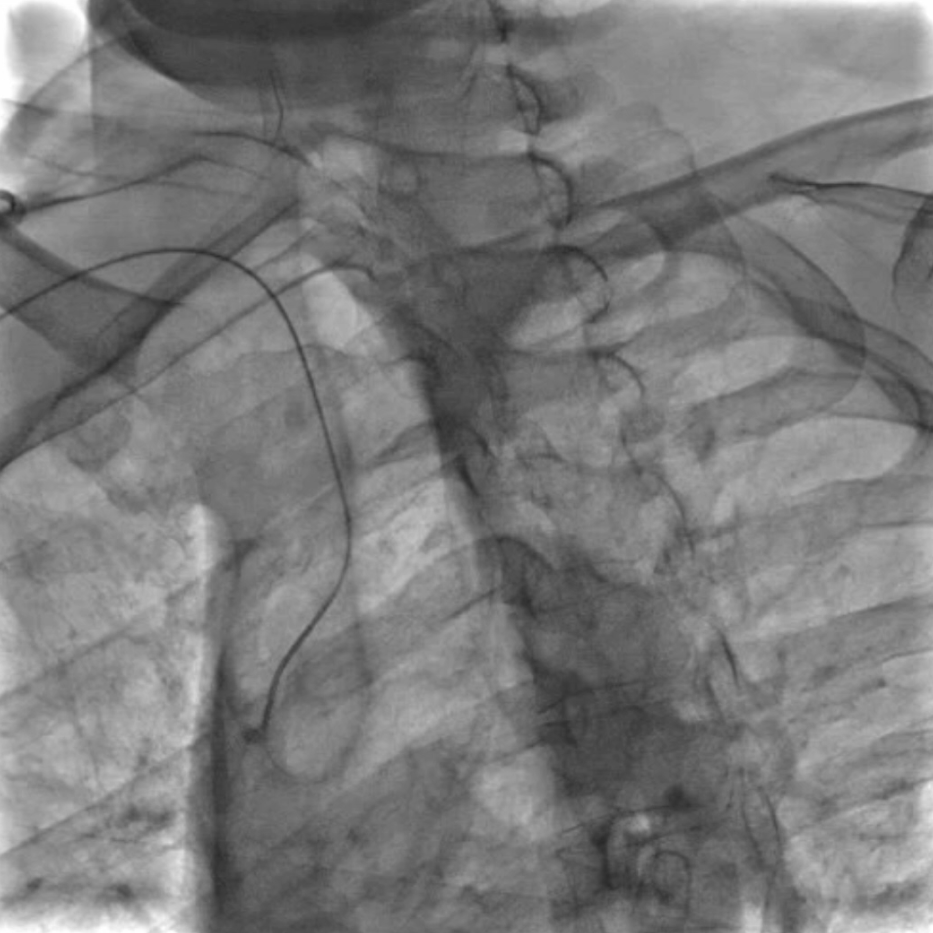

通路建立:精准操作减少血管损伤

穿刺与鞘管置入:局麻下穿刺右侧桡动脉,置入6F动脉鞘;

导管塑形与定位:使用SIMMONS导管选择左侧颈总动脉,操作时需轻柔(避免导管头端触碰血管壁导致斑块脱落),通过“反八字”塑形可精准对接左侧颈总动脉,导管弯部挂于颈动脉分叉处提供稳定支撑;

长鞘置入:在左前斜位透视下送入90cm长鞘,全程观察方向以避免阻力过大导致血管损伤